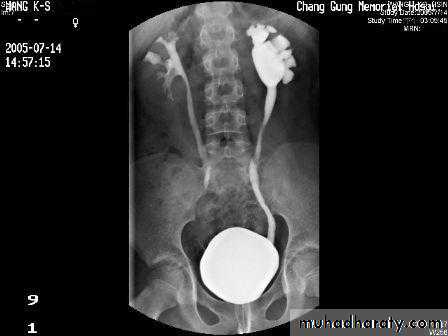

male &female reproductive tractsmammogram

genital tract and mammogram